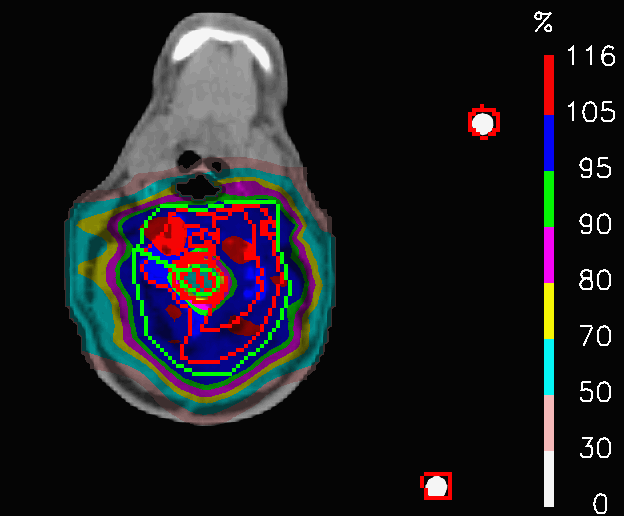

The case of a treatment with fields crossing the nasal cavity has been taken into consideration. The field directions of the nominal plan are shown in Fig.3; the frontal fields F1 and F2 encounter the nasal cavity to reach the target volume. To evaluate the stability of the IMPT plan, first, the original CT image was modified to simulate the extreme scenarios, of the cavity being completely empty (HU = 0) and filled with mucus (HU similar-to-or-equals\simeq 30), as shown in Fig.4; the original plan (PLAN-NOM) and the plan with OL penalization (PLAN-OL), where an OL (0,1)absent01\in(0,1) was selected for the nose VOI, were re-computed for both extreme scenarios, to evaluate the potential variation range with respect to the planning CT. We named PLAN-NOM-H and PLAN-NOM-L, respectively, the difference between the nominal plan recomputed on the CT with low and high density nasal cavity and the plan computed on the original CT and we did similarly for the extreme scenario plans with OL penalization (PLAN-OL-H and PLAN-OL-L).

(a) Axial CT slice

(b) Azimuthal CT slice

Figure 3: Fields crossing the nasal cavities: axial and azimuthal CT slice of the nasal cavity plan showing the red contour of the PTV; the fields F1, F2 and F3 involved in the treatment are also shown.